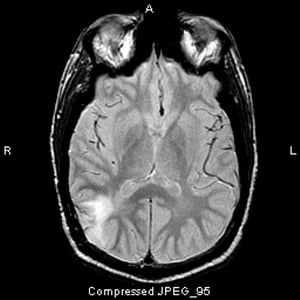

Questa scansione RM T2-FLAIR (fluid-attenuating inversion recovery) mostra un segnale bianco nel lobo temporale posteriore. Il segnale non è potenziato dal contrasto. È un astrocitoma anaplastico (grado III).

Image courtesy of William R. Shapiro, MD.